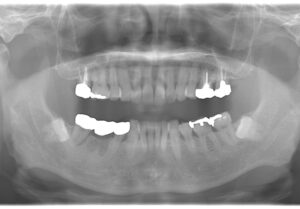

術前・術後写真

【術前】

右下7番の状態が悪い患者さんでした。骨吸収を起こしており動揺もでていたので、抜歯も考えましたが、インプラントを選択されたので、骨吸収像は見られますが、動揺はほぼ無くなり噛めている状態を維持されています。インプラントは他の歯を守ることができる治療法だと思えた症例となりました。